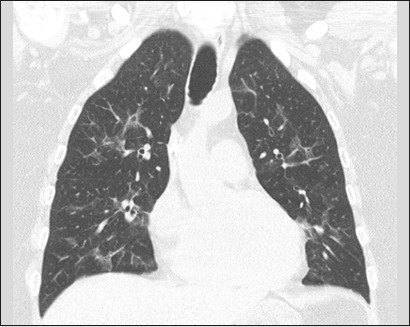

Results: Forty-nine patients (30 males; mean age, 61 years) were included. We identified Gram-negative bacteria in 45 patients, Gram-positive bacteria in 13, and fungi in three. Pulmonary abnormalities were bilateral in 73% of the patients in the sample, and there was no difference in prevalence between the upper and lower lung fields in 53%. Common alterations were consolidation, in 73% of the patients, bronchial wall thickening, in 71%, bronchiectasis, in 55%, and nodules, in 53%; extrapulmonary findings were less common, being identified in ≤ 27%. Pulmonary findings were typically bilateral and without a predominance between the upper and lower lung fields (p < 0.05). Common associations were between consolidation and bronchiectasis, between nodules and bronchial wall thickening, and between bronchiectasis and bronchial wall thickening (p < 0.05 for all).

Conclusion: The CT manifestations of pneumonia in patients with hematologic diseases not responding to empirical therapy can resemble those of lobular pneumonia with airway inflammation. For that reason, as well as because multiple pathogens can be present in the same patient, examination of bronchoalveolar lavage fluid can be necessary.